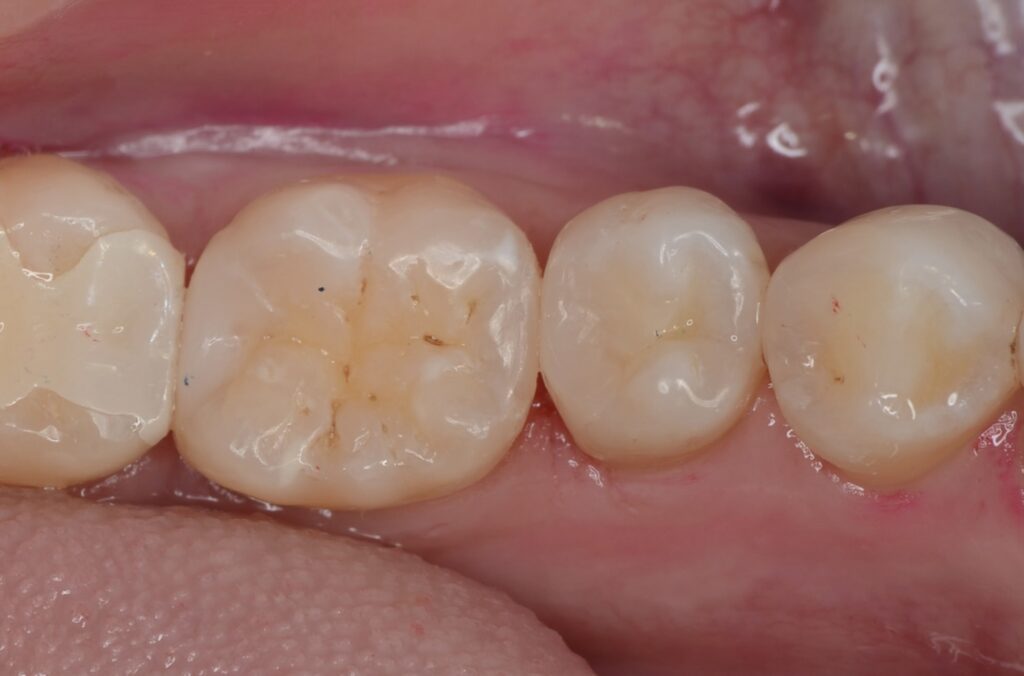

40代 虫歯治療 ダイレクトボンディング #51

Before

After

| 年齢 | 40代 | 治療方法 | ダイレクトボンディング |

|---|---|---|---|

| 性別 | 男性 | 通院回数 | 3回 |

| 主訴 | できるだけ歯を削る量を少なくしてむし歯を治したい | 費用 | 115,500円(税込) |

| 治療のメリット | 歯を削る量を少なくできる・自然な見た目・境目がピッタリできる | ||

| 治療のデメリット | 大きい虫歯治療には適応できない場合がある | ||